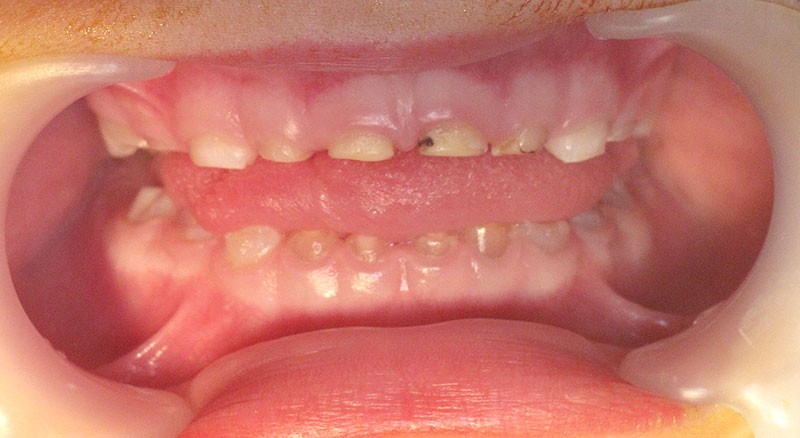

Teinte opalescente grise à jaune ambrée, couronnes globuleuses, calcifications intra-pulpaires, racines fines et courtes, attrition précoce, nécrose aseptique… Ces anomalies cliniques et radiographiques décrivent le tableau de la dentinogenèse imparfaite (DI) isolée de type 2. Cette anomalie génétique à transmission autosomique dominante est liée à un défaut de DSPP, gène de la sialophosphoprotéine dentinaire [1, 2]. Des anomalies dentinaires similaires résultent également de mutations de ce gène. Les avancées en recherche génétique tendent à réunir ces pathologies sous une même étiologie.

Un diagnostic précoce est primordial, car il existe aussi une forme associée à une anomalie osseuse, l’ostéogenèse imparfaite. Le chirurgien-dentiste est donc au premier plan pour dépister ces anomalies et limiter dès le plus jeune âge leurs conséquences infectieuses, fonctionnelles et esthétiques.